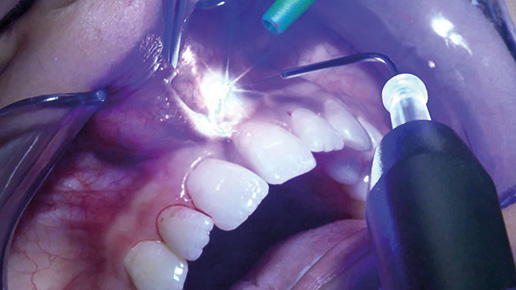

The application of diode laser SIROLaser Blue® in dentistry Streszczenie Technologie laserowe na stałe znalazły swoje miejsce w świecie medycyny. Ich rozwój zawdzięczamy wykorzystywaniu nowoczesnych rozwiązań technologicznych, dzięki którym stale zwiększa się spektrum zastosowań klinicznych laserów. Poza niewątpliwą skutecznością tych urządzeń bardzo ważną zaletą są pozytywne odczucia pacjentów, m.in. szybsza rekonwalescencja. Skonstruowanie wydajnej diody laserowej o niebieskim promieniowaniu umożliwiło lepszą absorpcję światła w tkance miękkiej oraz…